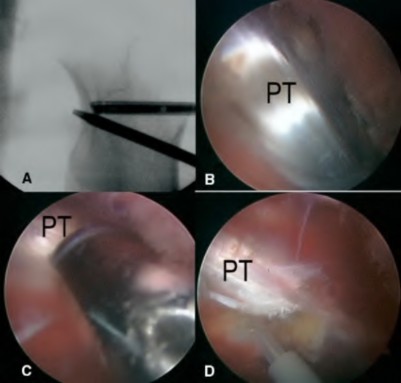

A patient presents with a palpable, painful 'catch' and an audible pop during active extension of the knee from 40 degrees to 30 degrees following a posterior-stabilized (PS) Total Knee Arthroplasty (TKA). What is the most likely etiology?

Explanation